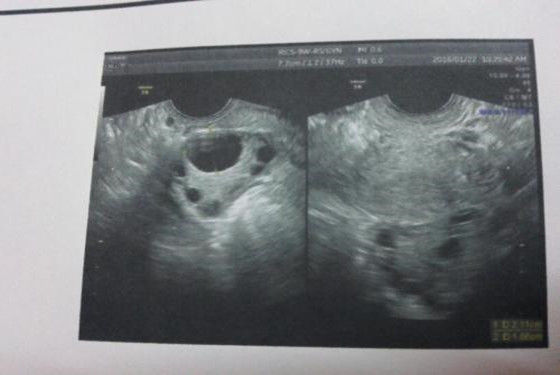

我是爻爻,备孕快5个月了可是一直没有结果,以前月经周期一直很准的,为了能尽快怀上孩子,也曾跑去医院做过卵泡监测,一次偶然的机会,听闺蜜说吃黑豆+跳绳,能够让卵泡长得又快又好,于是我就报着试一试的心情做做看。

我每天坚持吃两次黑豆,比如早上喝黑豆粥,下午就喝黑豆汤,另外,每天也坚持跳绳200下,天天坚持没漏掉一天不跳的,这样的饮食和习惯一直坚持了一个月。我以前都是6-7号排卵的,一次无意中晚上10点测试排卵居然强阳了,11点半左右我和老公就开始做功课,事后我趴着睡了20分钟,隔天早上起来我又用排卵试纸测了测,结果已经转弱了,这表示确定已经排卵了,于是,我暗地里高兴来着,为了保险起见,准备晚上和老公再补一次功课。